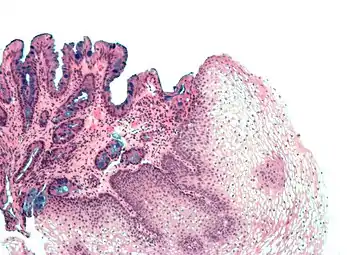

| Tinción hematoxilina-eosina | Bicomponente Anfifílica |

|

Tinción histológica general | ![]() |